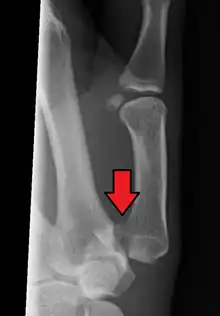

Bennett's fracture

Bennett fracture is a type of partial broken finger involving the base of the thumb, and extends into the carpometacarpal (CMC) joint.[1]

This intra-articular fracture is the most common type of fracture of the thumb, and is nearly always accompanied by some degree of subluxation or frank dislocation of the carpometacarpal joint.